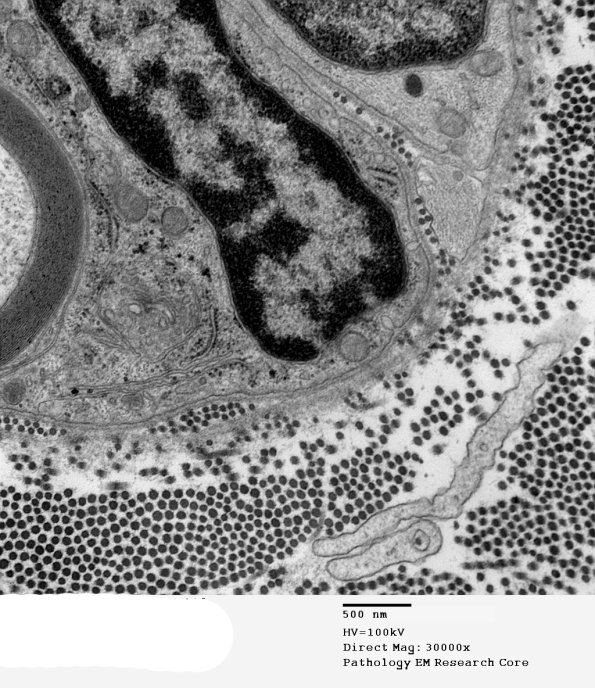

7A4 Axonal Degeneration (Case 10) EM 039 - Copy

Higher magnification of image #7A1. (electron micrograph)